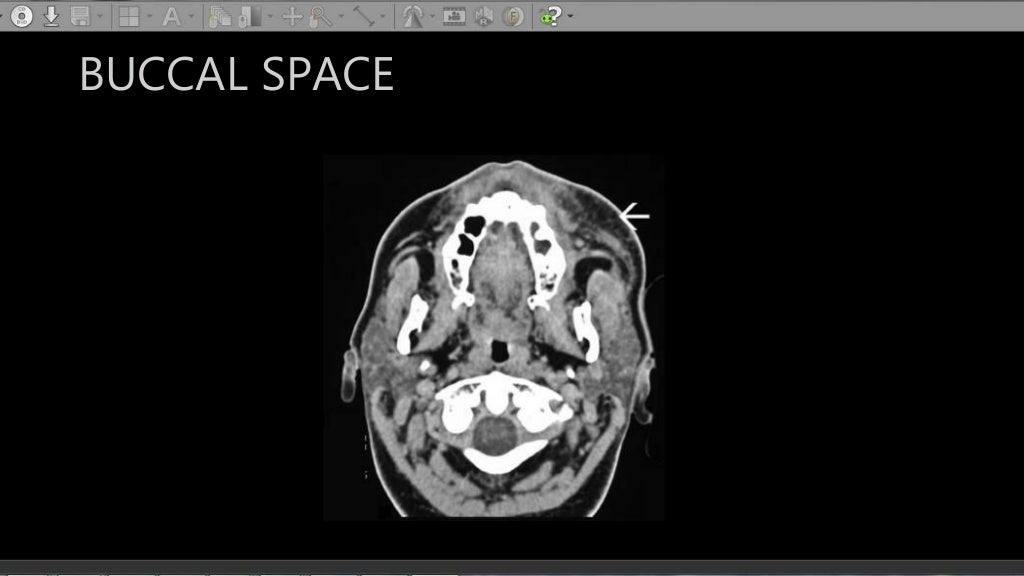

Ct Anatomy Of Neck Spaces . — the deep spaces of the head and neck refer to compartments delimited by the deep cervical fascia. in the suprahyoid region, the spaces of the neck include the sublingual space, submandibular space, peritonsillar space (pts), parapharyngeal space,. — neck spaces. five major spaces are easily identified in the infrahyoid neck: Visceral space (vs) carotid space (cs) retropharyngeal space (rps). the infrahyoid neck is divided into 5 major anatomical compartments or spaces by the various layers of the cervical fascia (2). Jan 20, 2017 | last update: scrollable ct highlighted the anatomy of the neck. 152 public playlists include this case. — publication date: 21 articles feature images from this case.